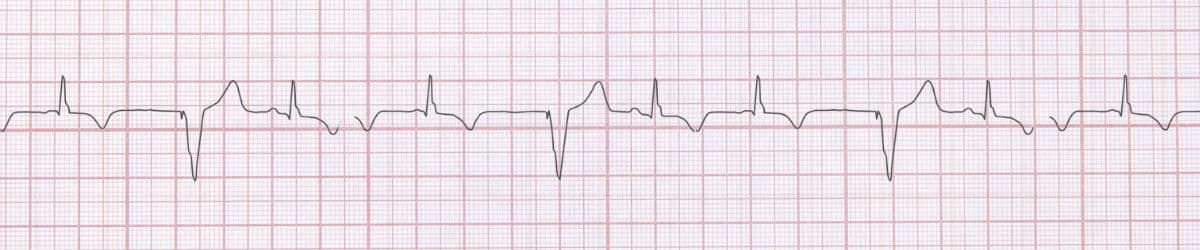

Normal Sinus Rhythm: ECG Recognition and Emergency Management

Comprehensive guide to recognizing and managing Normal Sinus Rhythm. Learn ECG criteria, clinical significance, evidence-based treatment, and common pitfalls. Written by Dr. Raj K, Emergency Medicine Physician.